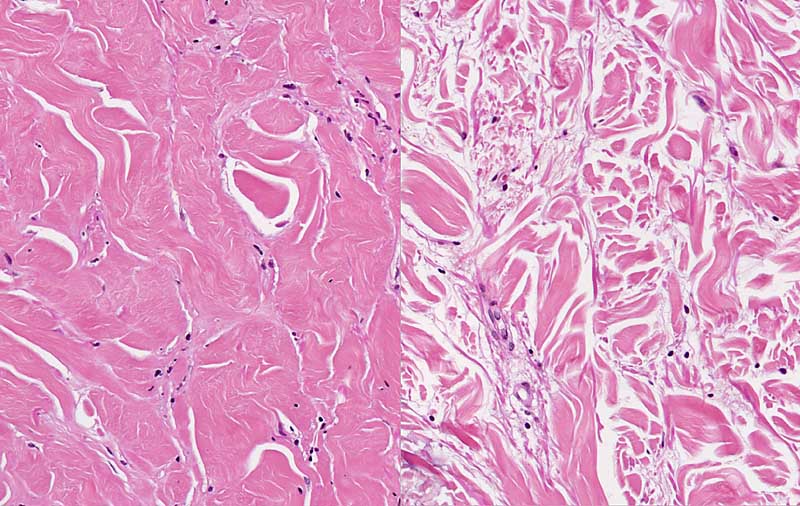

Morphea links, normale Dermis rechts

Verdickung, Verplumpung und Hyalinisierung der Kollagenfasern bei der Morphea (links). Normale retikuläre Dermis zum Vergleich rechts.

Mehrere indurierte Plaques an den Extremitäten mit weissem Zentrum und violettem Randsaum. Vereinzelt auch bullöse Läsionen.

Die Ursache der Morphea ist unbekannt. Der Plaque Typ der Morphea zeigt einen selbslimitierten Verlauf.